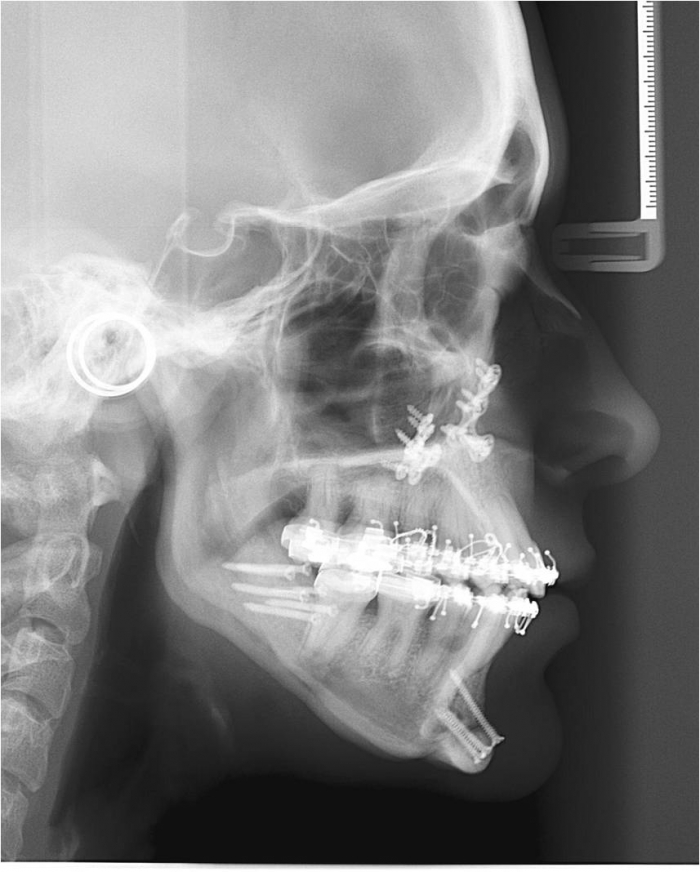

Telerradiografia inicial